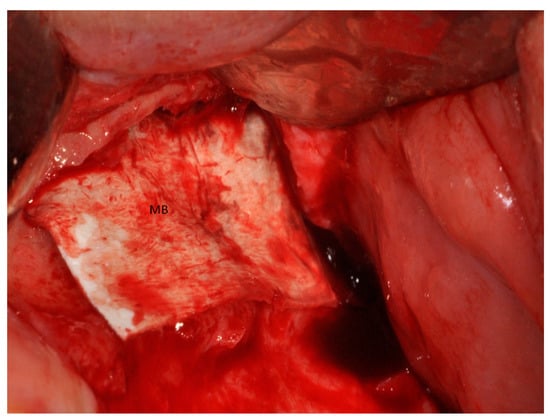

4. Materials and Methods